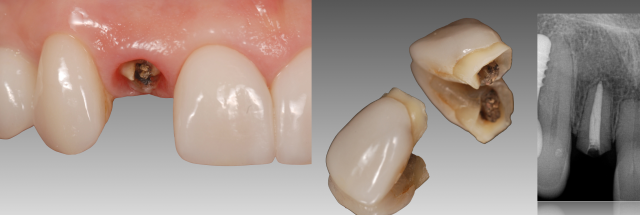

An abutment option that is often overlooked is a Custom UCLA-metal ceramic abutment. In my practice, I tend to use this abutment option more often than any other material. The UCLA abutment was introduced in 1987. It consists of a “gold cylinder” (that engages with the implant) and a plastic sleeve (that can be waxed and cast out of a high noble alloy and subsequently baked with ceramic). (Fig. 1)

The patient seen in Fig. 2 presented with a fractured lateral incisor. I had previously placed veneers on the anteriors eight years earlier.

The treatment plan was to extract the lateral incisor and place a single tooth implant. (Fig. 2) At the time of implant placement, the facial was treated with contour augmentation to help preserve the facial hard/soft tissue esthetics. (Buser et al. J Dent Res, 2013, Jensen et al. J Perio 2014)